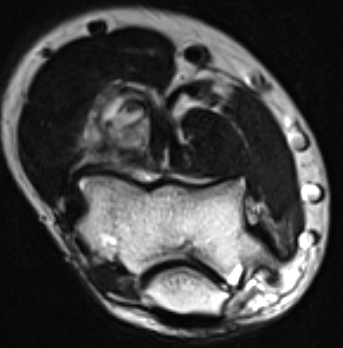

MRI

Heterogenous mass, low signal intensity T1, high signal intensity T2

- may have characteristic triple signal intensity

- area hyperintensity, isointensity and hypointensity

Knee

Heterogenous mass, not communicating with joint

DDx Baker's cyst